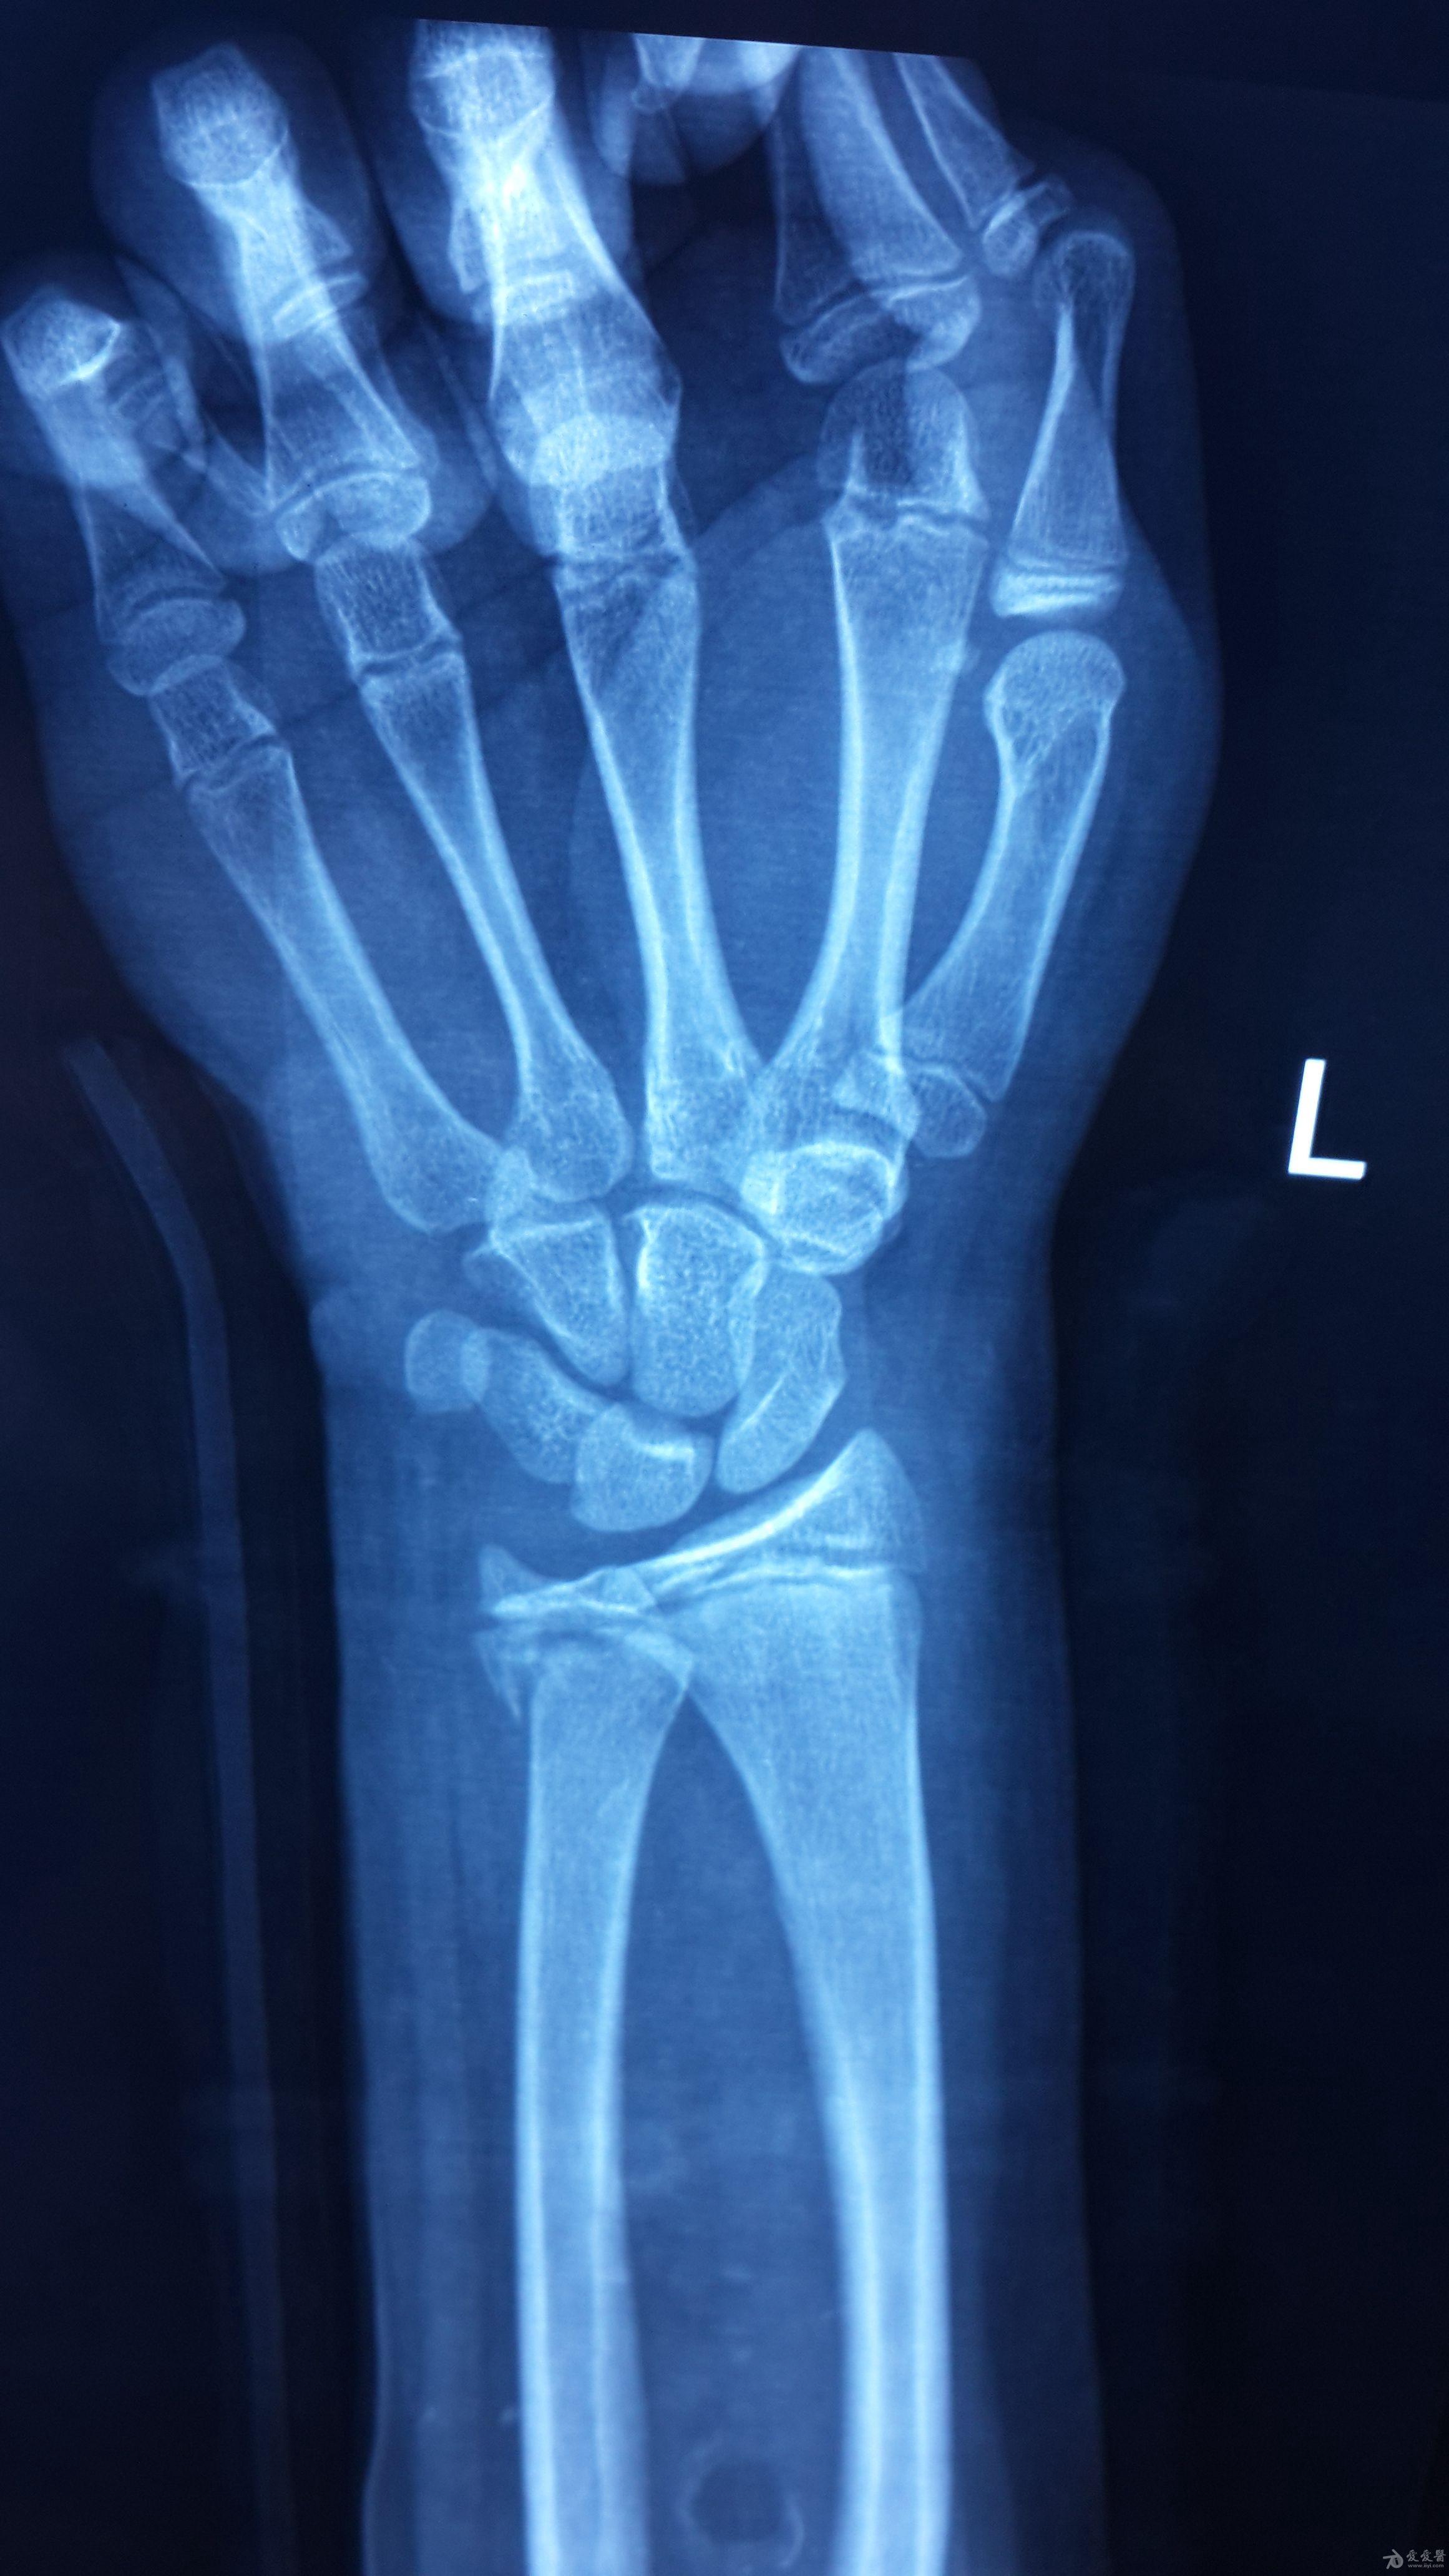

儿童盖氏骨折怎么治疗? [病例帖]

盖氏骨折一例